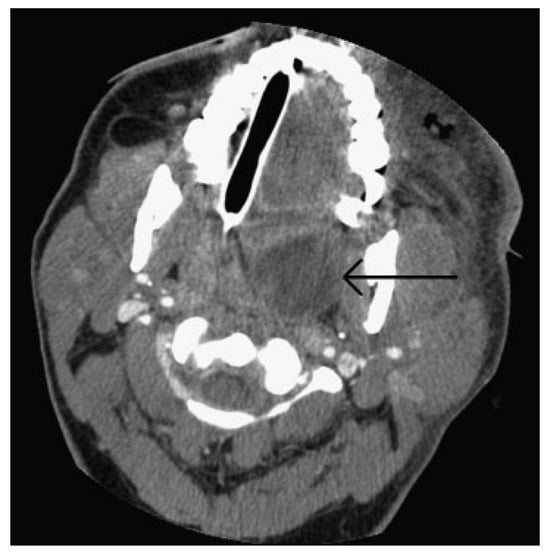

A 43-year-old woman presented to our clinic with a complaint of left sided facial pain and periorbital swelling secondary to her involvement in a motor vehicle collision the previous night. She reported no other injuries. Her medical history was significant for diabetes mellitus type II which was poorly controlled and hypertension for which she was taking metformin, glyburide, and lisinopril. The patient also had amblyopia in her left eye since childhood resulting in poor vision and diplopia. Her past surgical history was significant for cataract surgery of the left eye in 2009. A maxillofacial CT scan revealed a minimally displaced left orbital floor and medial orbital wall fractures (►Figure 1A). In the clinic, the patient was afebrile with stable vital signs. Her finger stick blood glucose (FSBG) was measured as 363. On physical examination, her left periorbita was edematous and she had tenderness to palpation of the left periorbital, temporal, and zygomatic regions, which were all consistent and normal with expected posttraumatic signs. Her vision in the right eye and left eye was 20/25 and 20/400, respectively, and the patient denied any acute visual acuity changes. Of note, 20/200 is considered legally blind in the United States. Bilateral extraocular movements were intact with no evidence of entrapment. Cranial nerve examination revealed grossly intact cranial nerves 3 to 12 with the exception being the left eye having vision changes of 20/400 and cranial nerve V2 paresthesia. Glasgow Coma Scale score was 15. The patient was prescribed pain medication, and asked to return to clinic in 4 days for reevaluation once the swelling subsided for surgical workup. The patient was sent to ophthalmology clinic that day and was evaluated. She was not prescribed antibiotics.

The patient was taken immediately to the operating room due to her worsening clinical presentation and the authors’ suspicion for necrotizing soft tissue infection. Incision and drainage and debridement of the necrotic tissue were performed on the left periorbital, zygomatic, and temporal regions (►Figure 3A–D). Copious purulent drainage was obtained which was submitted for Gram stain and cultures. Irrigation of the wound was then performed until no further murky fluid was appreciated with approximately 5 L of 0.9% normal saline. The wound was then packed in a standard wetto-dry fashion. The patient was placed on vancomycin, piper-acillin/tazobactam, and metronidazole and transferred to the intensive care unit (ICU) where she remained intubated and sedated. In the ICU, she was supported medically, including optimization of her blood glucose. Overnight, the patient remained tachycardic and febrile with a maximum temperature of 103°F (39.4 °C). At that time, a maxillofacial CT with contrast was obtained, which revealed left periorbital, orbital, and buccal inflammatory changes. Proptosis, lateral and downward displacement of the globe, and homogeneous opacification of the frontal, ethmoid, and maxillary sinuses were appreciated on the left side. The right ethmoid sinus was partially opacified, which justified the inflammatory changes in the right orbit. Additionally, a large fluid loculation of the left lateral pharyngeal space was present (►Figure 4). The intraoral examination revealed a large localized swelling of the left oropharynx and nasopharynx, with deviation of the palatal uvula from the midline. Ophthalmology was reconsulted. On postoperative day 2, the patient was taken back to the operating room for incision and drainage of the left maxillary sinus and left lateral pharyngeal space and washout of existing wound. An intraoral incision was made on the left posterior oropharynx and blunt dissection was performed to enter the left lateral pharyngeal space where approximately 15 mL of purulence was obtained and samples were sent for cultures and sensitivities. Three nonrestorable, grossly carious left maxillary posterior teeth were then extracted to negate any possible source of odontogenic infection; however, no purulence or periapical involvement of the teeth was evident upon extraction. This made an odontogenic cause of the infection unlikely. The left maxillary sinus was entered via a standard Caldwell-Luc approach to drain the fluid collection appreciated on CT and an additional 5 to 10 mL of purulence was obtained. After copious irrigation of the sites, two ½ inch Penrose drains were placed, one in the left maxillary sinus and the other in the left lateral pharyngeal space. The drains were then secured to the oral mucosa with sutures. Washout and redressing of the left periorbital wound was then performed and the patient returned to the ICU intubated. Laboratory values showed white blood cell count of 15.9 g/dL, hemoglobin of 12 g/dL, hematocrit of 36.4%, and platelet count of 226,000/µL. Chemistry showed sodium level of 134 mmol/L, potassium level of 3.5 mmol/L, chloride level of 97 mmol/L, bicarbonate level of 27 mmol/L, blood urea nitrogen level of 6 mg/dL, creatinine level of 0.7 mg/dL, and glucose level of 375 mg/dL. Hemoglobin A1C was 12.8 and C-reactive protein was 34.2 mg/dL. The patient’s previously recorded hemoglobin A1C was 13.0 recorded 26 months earlier at the medicine clinic showing long-term poor diabetic control. Over the next few days, the patient clinically improved and her vital signs stabilized with the exception of a persistent elevated temperature of 101°F. Cultures came back as group C β hemolytic Steptococcus and Proteus mirabilis. After consultation with the infectious disease service, the antibiotics were narrowed to ampicillin/sulbactam and clindamycin. A repeat CT scan was obtained on hospital day 5 and a loculation was noted at the superior and lateral aspect of the left orbit, suggestive of subperiosteal abscess (►Figure 5A,B). Ophthalmology service recommended no intervention for the left orbital subperiosteal abscess. However, as the patient was still having low-grade temperature of 101°F (38.3 °C), the authors took the patient back to the operating room for incision and drainage of this area. We approached the superior-lateral orbit via an existing incision, and approximately 5 mL of purulence was obtained. Postoperatively, the patient improved clinically, and became afebrile. The intraoral drains were removed, and after cons ultation with the wound nurse, the wet-to-dry dressing of the skin was changed to petroleum-impregnated gauze. Despite our objection, the patient remained intubated for a prolonged period due to the discomfort of the ICU team in extubating the patient. The patient was extubated on hospital day 12. On the day of discharge, examination revealed significant decrease in left periorbital swelling, decrease proptosis, and increase extraocular movement in all directions; however, she continued to have 20/400 vision in the left eye and diplopia. Due to the defect in the left upper and lower eyelids, a home care nurse was assigned for daily dressing changes. Intraoral examination demonstrated resolution of swelling of the oropharynx. A maxillofacial CT scan revealed resolution of the original fluid loculations and a patent airway. Throughout the postoperative hospital stay, the patient’s glucose level and blood pressure were controlled. The patient was discharged on hospital day 13 with oral antibiotics, amoxicillin/clavulanic acid, and clindamycin, as well as her home antihypertensive and diabetic medications. The patient was closely followed up and her condition continued to improve. At 4 months follow-up, the patient presented with resolution of facial swelling; had proptosis and eyelid ptosis, normal extraocular movements; and her baseline visual acuity of her left eye remained 20/400. The patient was seen 1 year postoperatively and had continued resolution of her wounds with appropriate wound closure; however, she had continued strabismus, ptosis of the upper and lower lid secondary to scar contraction, as well as left V2 paresthesia (►Figure 6A,B). The orbital wound continued to heal via secondary intention with anticipated reconstruction and scar revision in the near future.

In this case, we believe that the infection originated in the maxillary sinus and extended into the orbital cavity through the fractured orbital floor, resulting in preseptal and postseptal orbital cellulitis progressing to abscess. The infection then likely spread to the face via the ophthalmic and angular vein, reaching the left buccal space. The lack of host response secondary to uncontrolled diabetes mellitus may have contributed to further dissemination of the infection to two other ipsilateral spaces: (1) from the maxillary sinus to the nasal cavity through the medial maxillary sinus wall and (2) from the buccal to the parapharyngeal space through the pterygomandibular raphe, a ligamentous band of the buccopharyngeal fascia, located between the superior pharyngeal constrictor and the middle portion of the buccinator muscles (►Figure 1B).

Figure 1. (A) Coronal computed tomographic scan showing minimally displaced left orbital floor and medial wall fractures, total opacification of left maxillary and ethmoid sinuses, and partial opacification of frontal sinus. Healed previous injury to right medial orbital wall was noted. (B) Route of infection extending from maxillary sinus to orbit, nasal cavity, ethmoid sinus, buccal space, and parapharyngeal space.